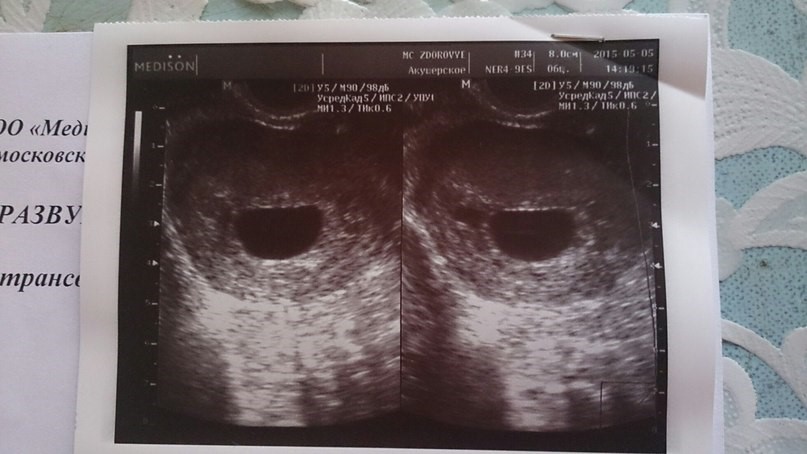

- УЗИ, во время которого не прослушивается биение сердца плода, наблюдается анэмбриония;

УЗИ на ранних сроках является наиболее достоверным методом определения патологии, который позволяет вовремя обнаружить: несоответствие размеров матки текущим срокам, отсутствие сердечного ритма и дыхания, остановку роста эмбриона, неправильное его положение и деформацию контуров вокруг тела плода, что может свидетельствовать о процессе разложения.

Показатели УЗИ

- Сердцебиение эмбриона не определяется. В норме на ультразвуковом исследовании оно заметно, начиная с 5 недели беременности.

- Плодное яйцо не имеет диаметра таких размеров, которые предполагает срок беременности.

- Величина эмбриона, находящегося в плодном яйце, не соответствует сроку беременности.

- Если срок до 4 недель, то признаком гибели плодного яйца является деформация.

- Эмбрион не визуализируется на сроке 6 – 7 недель.

Самым точным способом определения замершей беременности и на ранних сроках, и на поздних, является УЗИ, в ходе которого специалист будет проверять:

- Несоответствие размера матки сроку беременности.

- Отсутствие сердцебиения и дыхательных движений.

- Неправильное положение, деформация и контур вокруг тела плода на поздних сроках, свидетельствующий о разложении тканей.

- Отсутствие визуализации и роста эмбриона на ранних сроках беременности. Очень редко, но бывает и так, что плодное яйцо еще какое-то время растет, а эмбрион в нем не формируется или остановился в развитии.